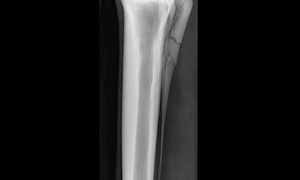

骨折部の変化 ~ 骨片の転位(dislocation)

骨片の転位骨折をおこした外力の余力によっておこる骨折端の転位を、一次性転位(primary dislocation)といいます。しかし、骨片の転位はまた、患部の負重、筋肉の収縮、他動運動、患畜の輸送などによって、随意的または不随意的にも発生...